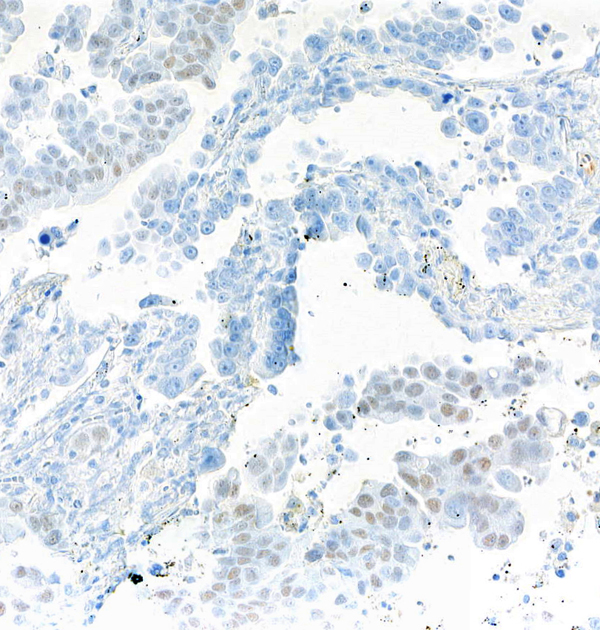

IHC (Immunohistochemisry)

(Detection of human SOX2 by immunohistochemistry. Sample: FFPE section of lung carcinoma. Antibody: Mouse anti-SOX2 monoclonal antibody [BC36] (AAA213516-1). Secondary: HRP-conjugated goat anti-mouse IgG .)